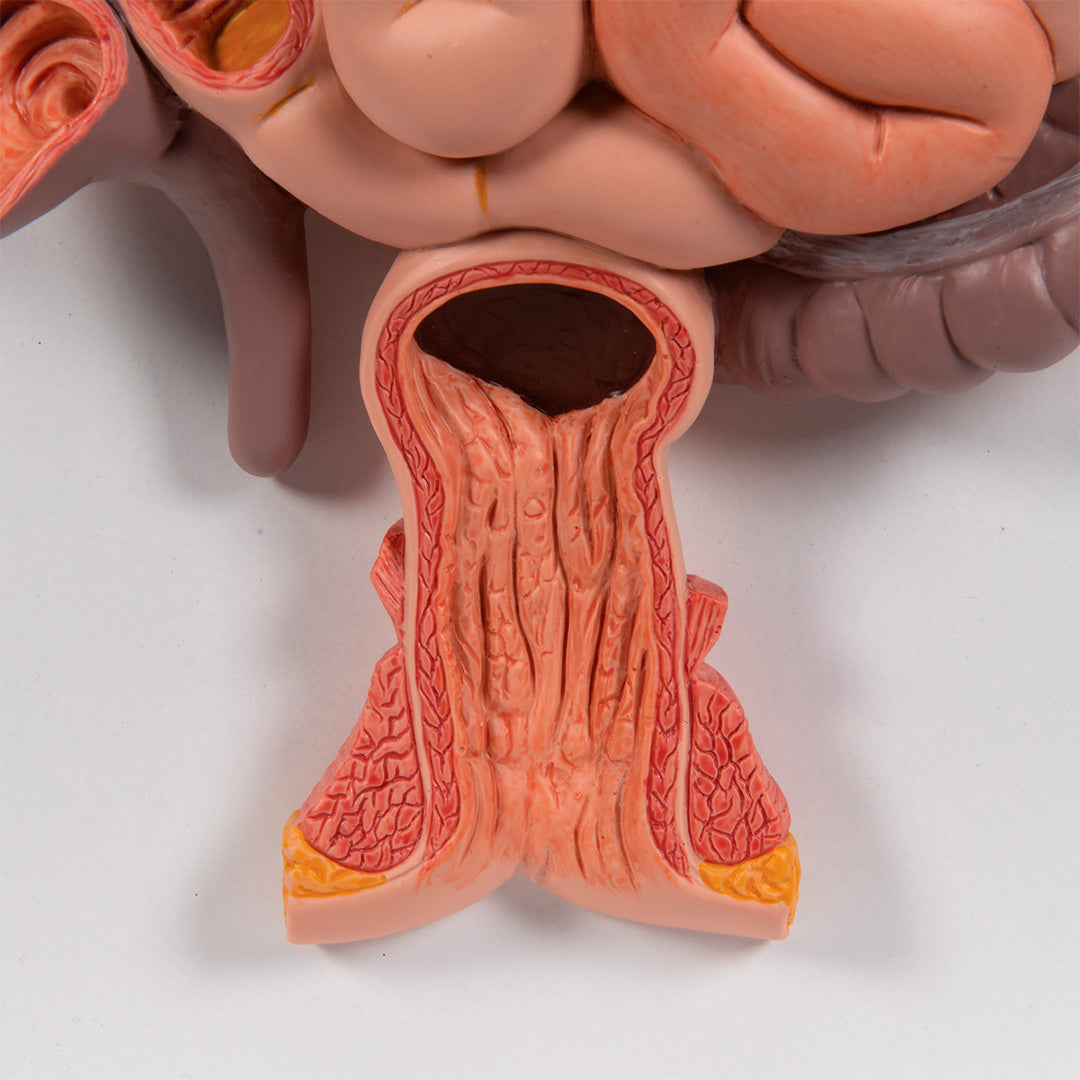

El duodeno, el ciego y el recto están abiertos.